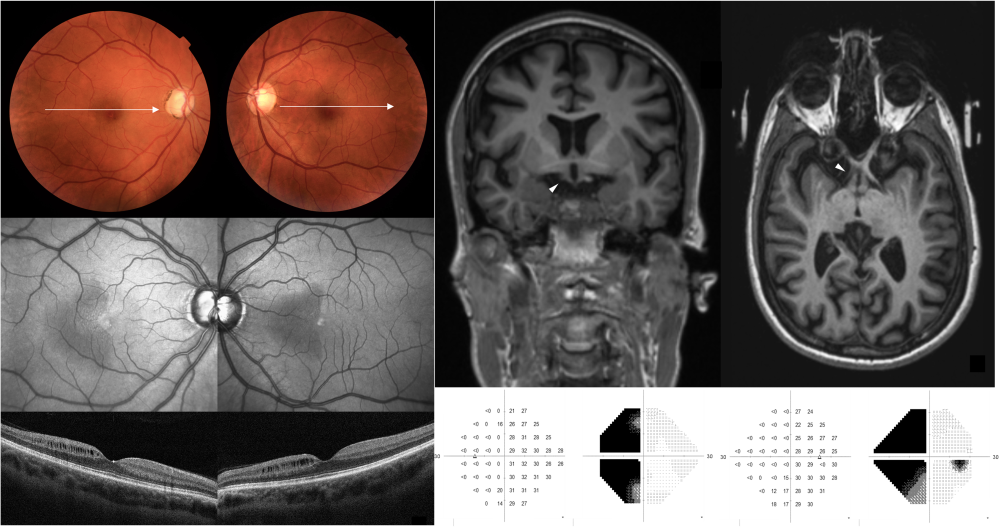

Título: Retinal imprint of optic tract injury

Autor: Telma Machado

Coautores: Raquel Félix, Henrique C. Queirós, Miguel Raimundo, Pedro Fonseca

Instituição: Hospitais da Universidade de Coimbra, ULS Coimbra

Descrição: Near-infrared reflectance and macular optical coherence tomography reveal semilunar hyporeflective areas corresponding to microcystic changes within the retinal inner nuclear layer. These changes involve the temporal hemiretina of the right eye and nasal hemiretina of the left eye, respecting the vertical meridian and correlating with a left homonymous hemianopia.